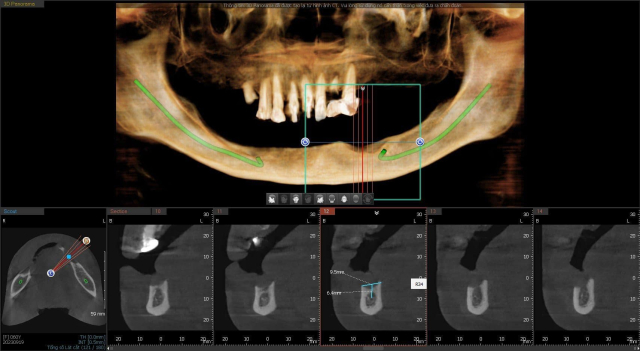

Điều này rất quan trọng, nó cũng là một phần quyết định đến kết quả của ca cấy ghép. Vì chỉ có chụp phim cắt lớp 3 chiều CT Conebeam mới có thể xem xét mức độ tiêu xương hàm, đánh giá các cấu trúc giải phẫu lân cận, từ đó mới chọn trụ Implant phù hợp và lên hướng đặt trụ chính xác. Còn chụp X quang thông thường sẽ không thể làm được những điều trên nên sẽ rất nguy hiểm.

Bước tiếp theo là chụp phim CT 3D để kiểm tra chiều cao và rộng của xương tại vị trí răng đã mất. Từ đó lên kế hoạch điều trị và lựa chọn trụ Implant. Nếu trường hợp xương hàm không đủ điều kiện để cắm trụ Implant thì sẽ tiến hành ghép xương, nâng xoang,….

Hình ảnh chụp CT răng khảo sát cấu trúc và khối lượng xương hàm trước khi trồng răng implant